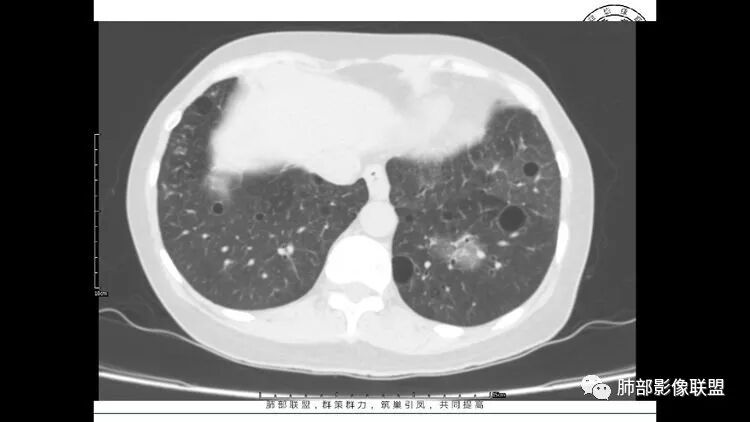

老年女性,眼炎入院,血常规正常,双肺多发囊状影,病变随机分布,形态单一,与血管关系密切,考虑LIP。左下肺混合GGO,边界尚清,贴近囊腔,鉴别腺癌。炎症指标无异常暂不考虑感染性病变。

胸CT:1.双肺多发囊性变,以中下肺为主,病变边缘可见肺动脉,部分囊内可见分隔及肺动脉,双下部分肺野周围可见小叶中心结节及树丫征。

2 左肺上叶尖后段 右肺上叶前段 右肺下叶外基底段 结节影,边界清楚,可见柔软毛刺,左肺下叶后基底段混合密度影。

3.纵隔淋巴结肿大?,以主动脉弓为界向上向下增大。

考虑:淋巴瘤肺浸润,眼部症状考虑与此有关;LIP?;继续鉴别肺腺癌?血管炎?。

患者中年女性,因右眼红痛1天就诊。胸CT:双肺多发囊性变及结节影,囊以中下肺为多,部分囊内可见分隔及肺动脉,结节部分为实性,部分为混合性,边缘光滑,未见明显毛刺、棘突、胸膜牵拉及血管集束征象。双中下可见支气管扩张及树丫征。淋巴结无明显肿大。综合考虑:一元淋巴细胞间质性肺炎。多元鉴别肺腺癌并转移等恶性病变。

LIP影像重要线索一句话:

双肺下叶分布为主的间质改变(磨玻璃影、小叶间隔增厚)、散在气囊影(常有血管贴边)、边界不清小结节